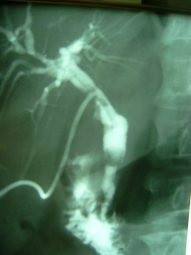

Litotripsia y extracción de cálculo de coledoco residual

Envíado por Dr. Carlos Miguel Zavaleta Consuegra